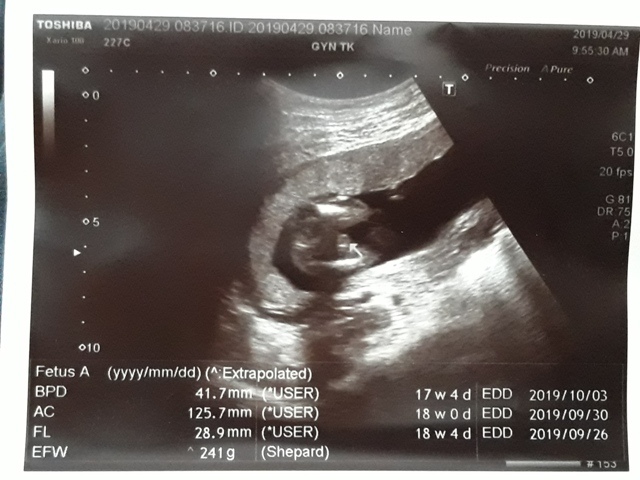

| 仙人掌(2019/04/29)的真心話 星期一 天氣晴 編號19-110 |

近三次產檢資料統計

| 日期/項目 | BPD | AC | FL | EFW | 心跳 |

| 2019年03月04日 | 無資料 | 無資料 | 無資料 | 無資料 | 無資料 |

| 2019年04月01日 | 28.9mm | 77.9mm | 14.2mm | 107g | 153 |

| 2019年04月29日 | 41.7mm(44%) | 125.7mm(61%) | 28.9mm(103%) | 241g(125%) | 150 |

| BPD:胎兒頭骨橫徑 AC:胎兒腹圍的長度 FL:胎兒大腿骨的長度 EFW:胎兒的體重 | |||||